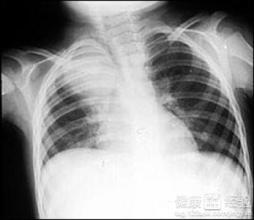

某个早晨,咳嗽和发热的症状让我陷入恐慌,迅速前往医院后,经过一系列检查,医生告知我:“你得了最新肺炎。”那一刻,我仿佛跌入了深渊,但面对现实,我必须坚强,我深知,我不能放弃自己,不能放弃家人和朋友。